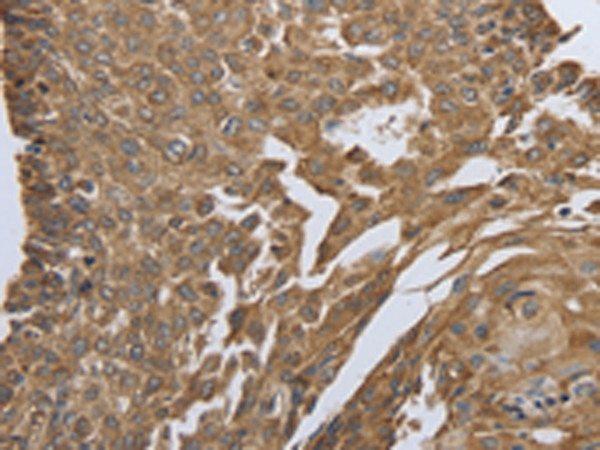

分类: 科研抗体货号: P11103别名: 123F2; RDA32; NORE2A; RASSF1A; REH3P21应用: WB,IHC反应种属: Human, Mouse